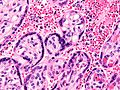

English: Very high magnification micrograph of maternal malaria. Placenta. H&E stain.

The images show organisms within the red blood cells. Related images

Syncytiotrophoblast.

Fetal red blood cell.